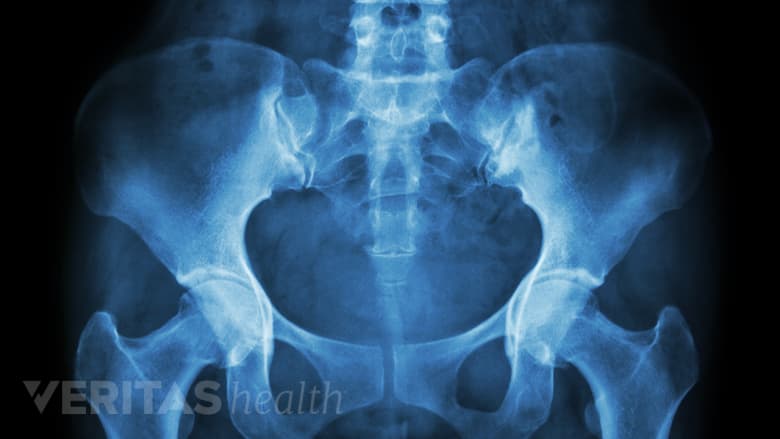

Women may have a higher chance of developing coccydynia due to a wider pelvic angle.

Women have a higher chance of developing coccydynia than men, due to a wider pelvic angle as well as trauma to the coccyx endured during childbirth.